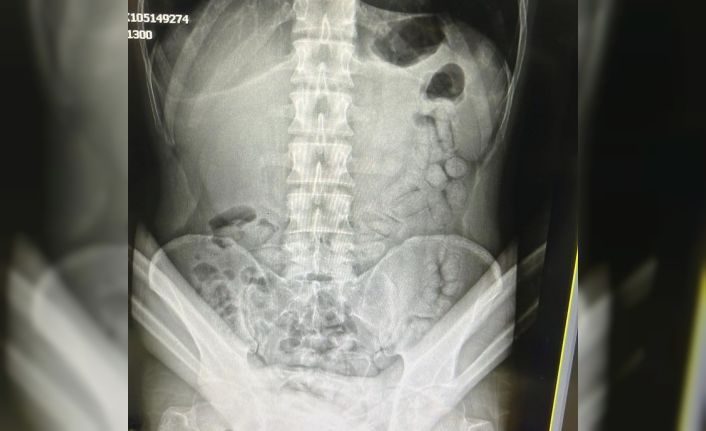

Adli makamların talimatı üzerine Gümüşhane Devlet Hastanesine götürülen şahsa yönelik iç beden muayenesinde bağırsaklarında 55 adet kapsül olduğu tespit edildi. Hastanede yapılan müdahalenin ardından şahsın bağırsaklarından çıkarılan kapsüllerin içerisinde toplamda 317,46 gram metamfetamin ele geçirildi.